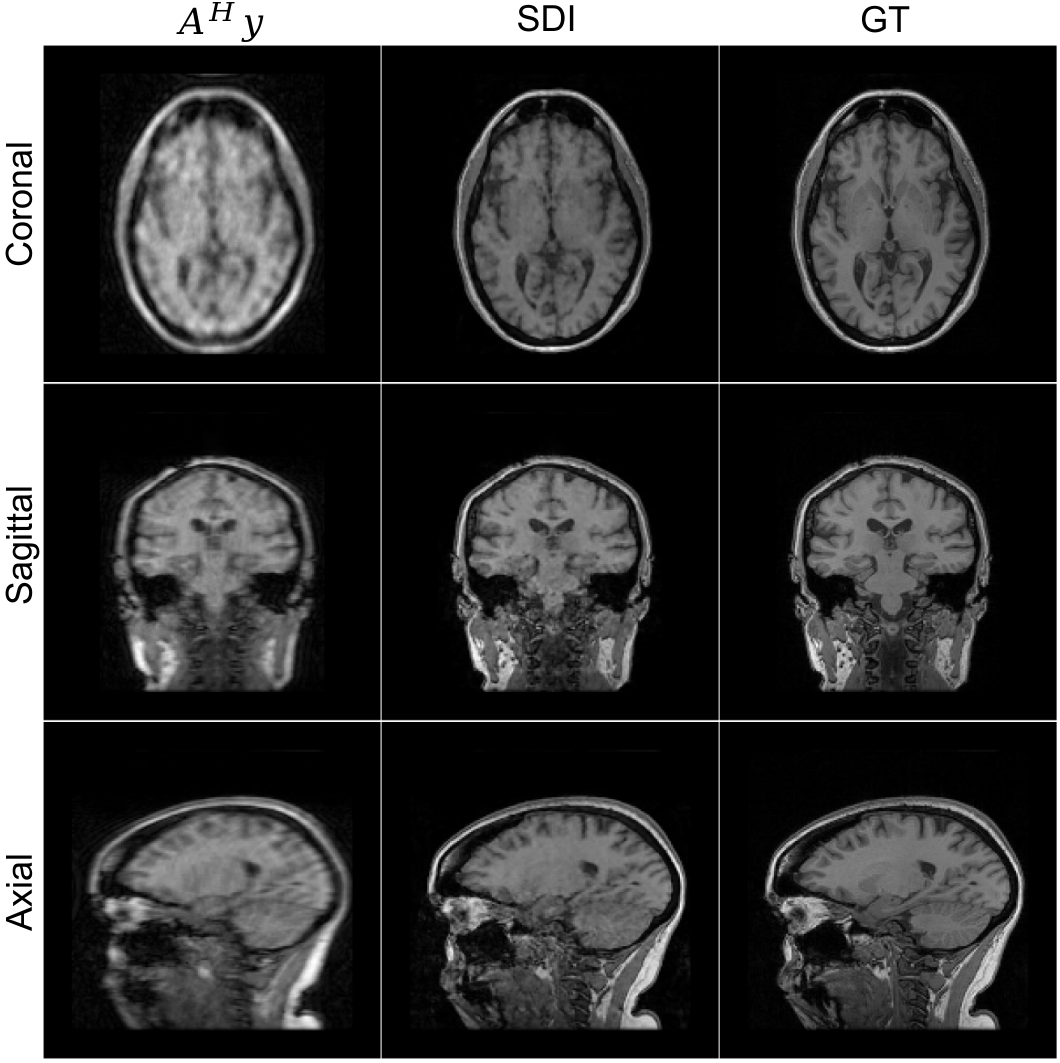

To further demonstrate the flexibility of self-diffusion, we apply it to the reconstruction of volumetric 3D MRI data from undersampled k-space measurements. This task poses additional challenges due to the increased dimensionality and the need for spatial coherence across slices. We consider a 12-coil 3D T1-weighted brain scan and apply a Cartesian undersampling mask on the k-space that has a dimension of 160×\times160×\times128. The undersampling mask is generated using BART’s command poisson with an acceleration factor of 2.5 along two phase-encoding directions. This leads to a total acceleration factor of 8. The coil sensitivities are estimated using BART’s command ecalib. The measurements 𝐲\mathbf{y} are formed with 𝒜\mathcal{A}, which consists of the undersampling mask, 3D Fourier transform, and coil sensitivities. To accommodate 3D dimensionality, we adapt the denoising network to a 3D U-Net architecture with 3D convolutional layers and which is initialized in the same way as the 2D U-Net. The parameters for Algorithm˜1 are {T=40;K=50;η=0.001}\{T=40;K=50;\eta=0.001\} and Adam optimizer is used. Figure 9 shows the reconstructed sagittal, coronal, and axial slices.

Refer to caption

Figure 9: Reconstruction of a 3D T1-weighted brain MRI using self-diffusion from 8×\times undersampled measurements. Shown are sagittal, coronal, and axial slices, demonstrating sharp anatomical structures and minimal artifacts. The initial measurement (𝒜H𝐲\mathcal{A}^{H}\mathbf{y}), self-diffusion inference (SDI), and ground truth (GT).